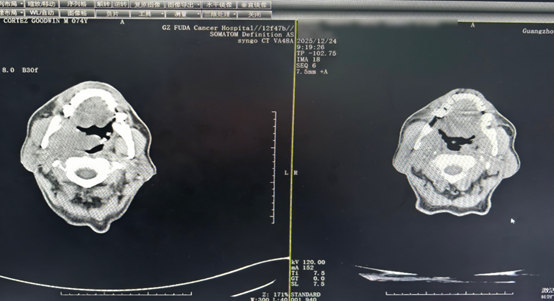

Perbandingan CT setelah dua siklus pengobatan menunjukkan pengurangan tumor orofaringeal dan massa serviks.